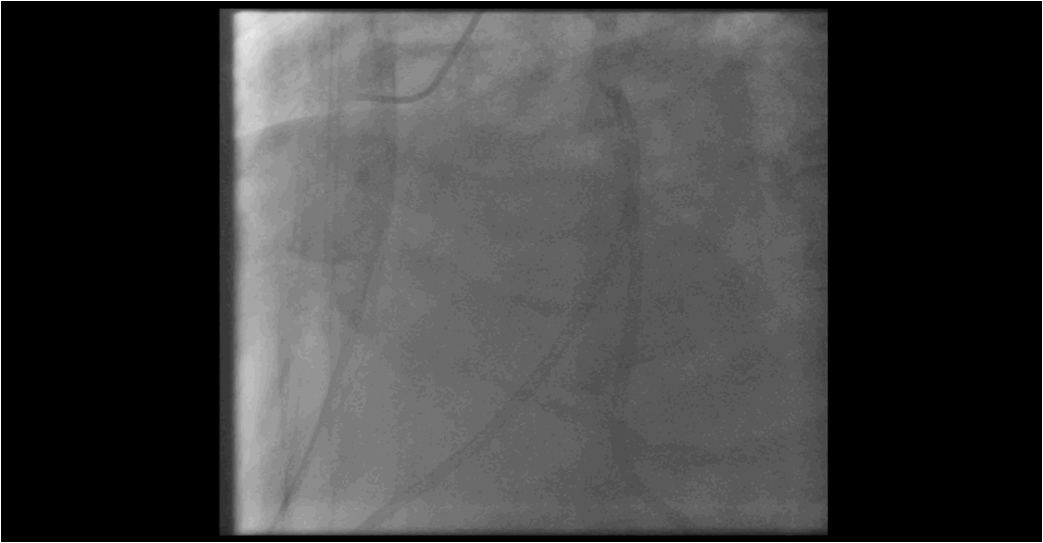

患者心衰纠正不理想,药物治疗效果欠佳,经讨论后,拟行PCI介入治疗

考虑到患者心功能差,存在术中不能耐受的可能,提前准备IABP及呼吸机,备术中必要时使用。